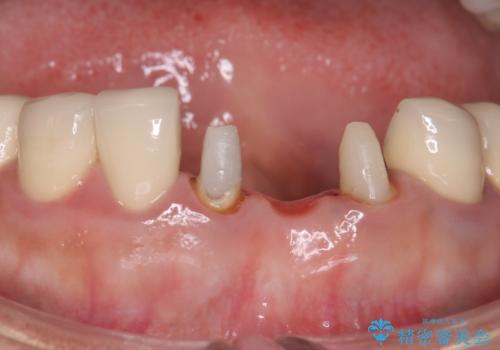

- 下の前歯のかぶせ物がが一つとれてしまい、他院で仮歯を装着されてから来院されました。

仮歯をはずし確認すると、一本の歯が土台ごとはずれて根だけになってしまって、保存が難しい状態でした。

抜歯後にブリッジを装着する計画としました。